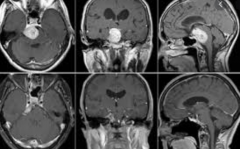

颅咽管瘤全切除有可能吗?如何避免术后复发?颅咽管瘤(cran...

晓米(化名)已经6岁了,但相对比同龄的小朋友她的个子矮了许...